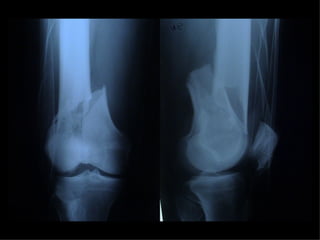

A B C Distal femoral fractures type C Choosing the right strategy and the right implant

INDICAZIONI COMUNI Fratture sovracondiloidee Fratture intercondiliodee Fratture diafisarie distali PARTICOLARI Fratture con grave osteoporosi Fratture periprotesiche